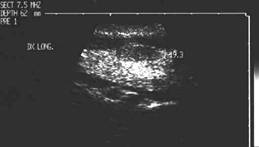

Lob drept, proiectie trasversala si longitudinala.

Femeie de 34 ani. Cunoscute cu hipertiroidism in

cadrul maladiei Graves.

Nodul paraistmic anterior dr. de 11x20x19mm (2 cc), cu margini nedefinite prin

absenta haloului periferic, neomogene, hipoecogen, care deformeaza conturul anterior

al glandei.

Examen citologic: carcinom papilar. Confirmare histologica (carcinom papilar multifocal cu metastaze linfonodale).